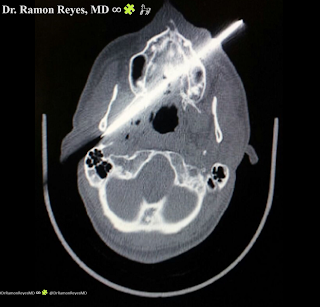

Imagen de tomografía axial computarizada (TAC) donde se muestra cuerpo extraño (cuchillo) que se introduce por región maxilar izquierda atravesando paladar duro y cavidad oral. Su punta provoca una subluxación de la articulación temporomandibular y lesión parafaríngea derecha con burbujas aéreas.

Figura 2.